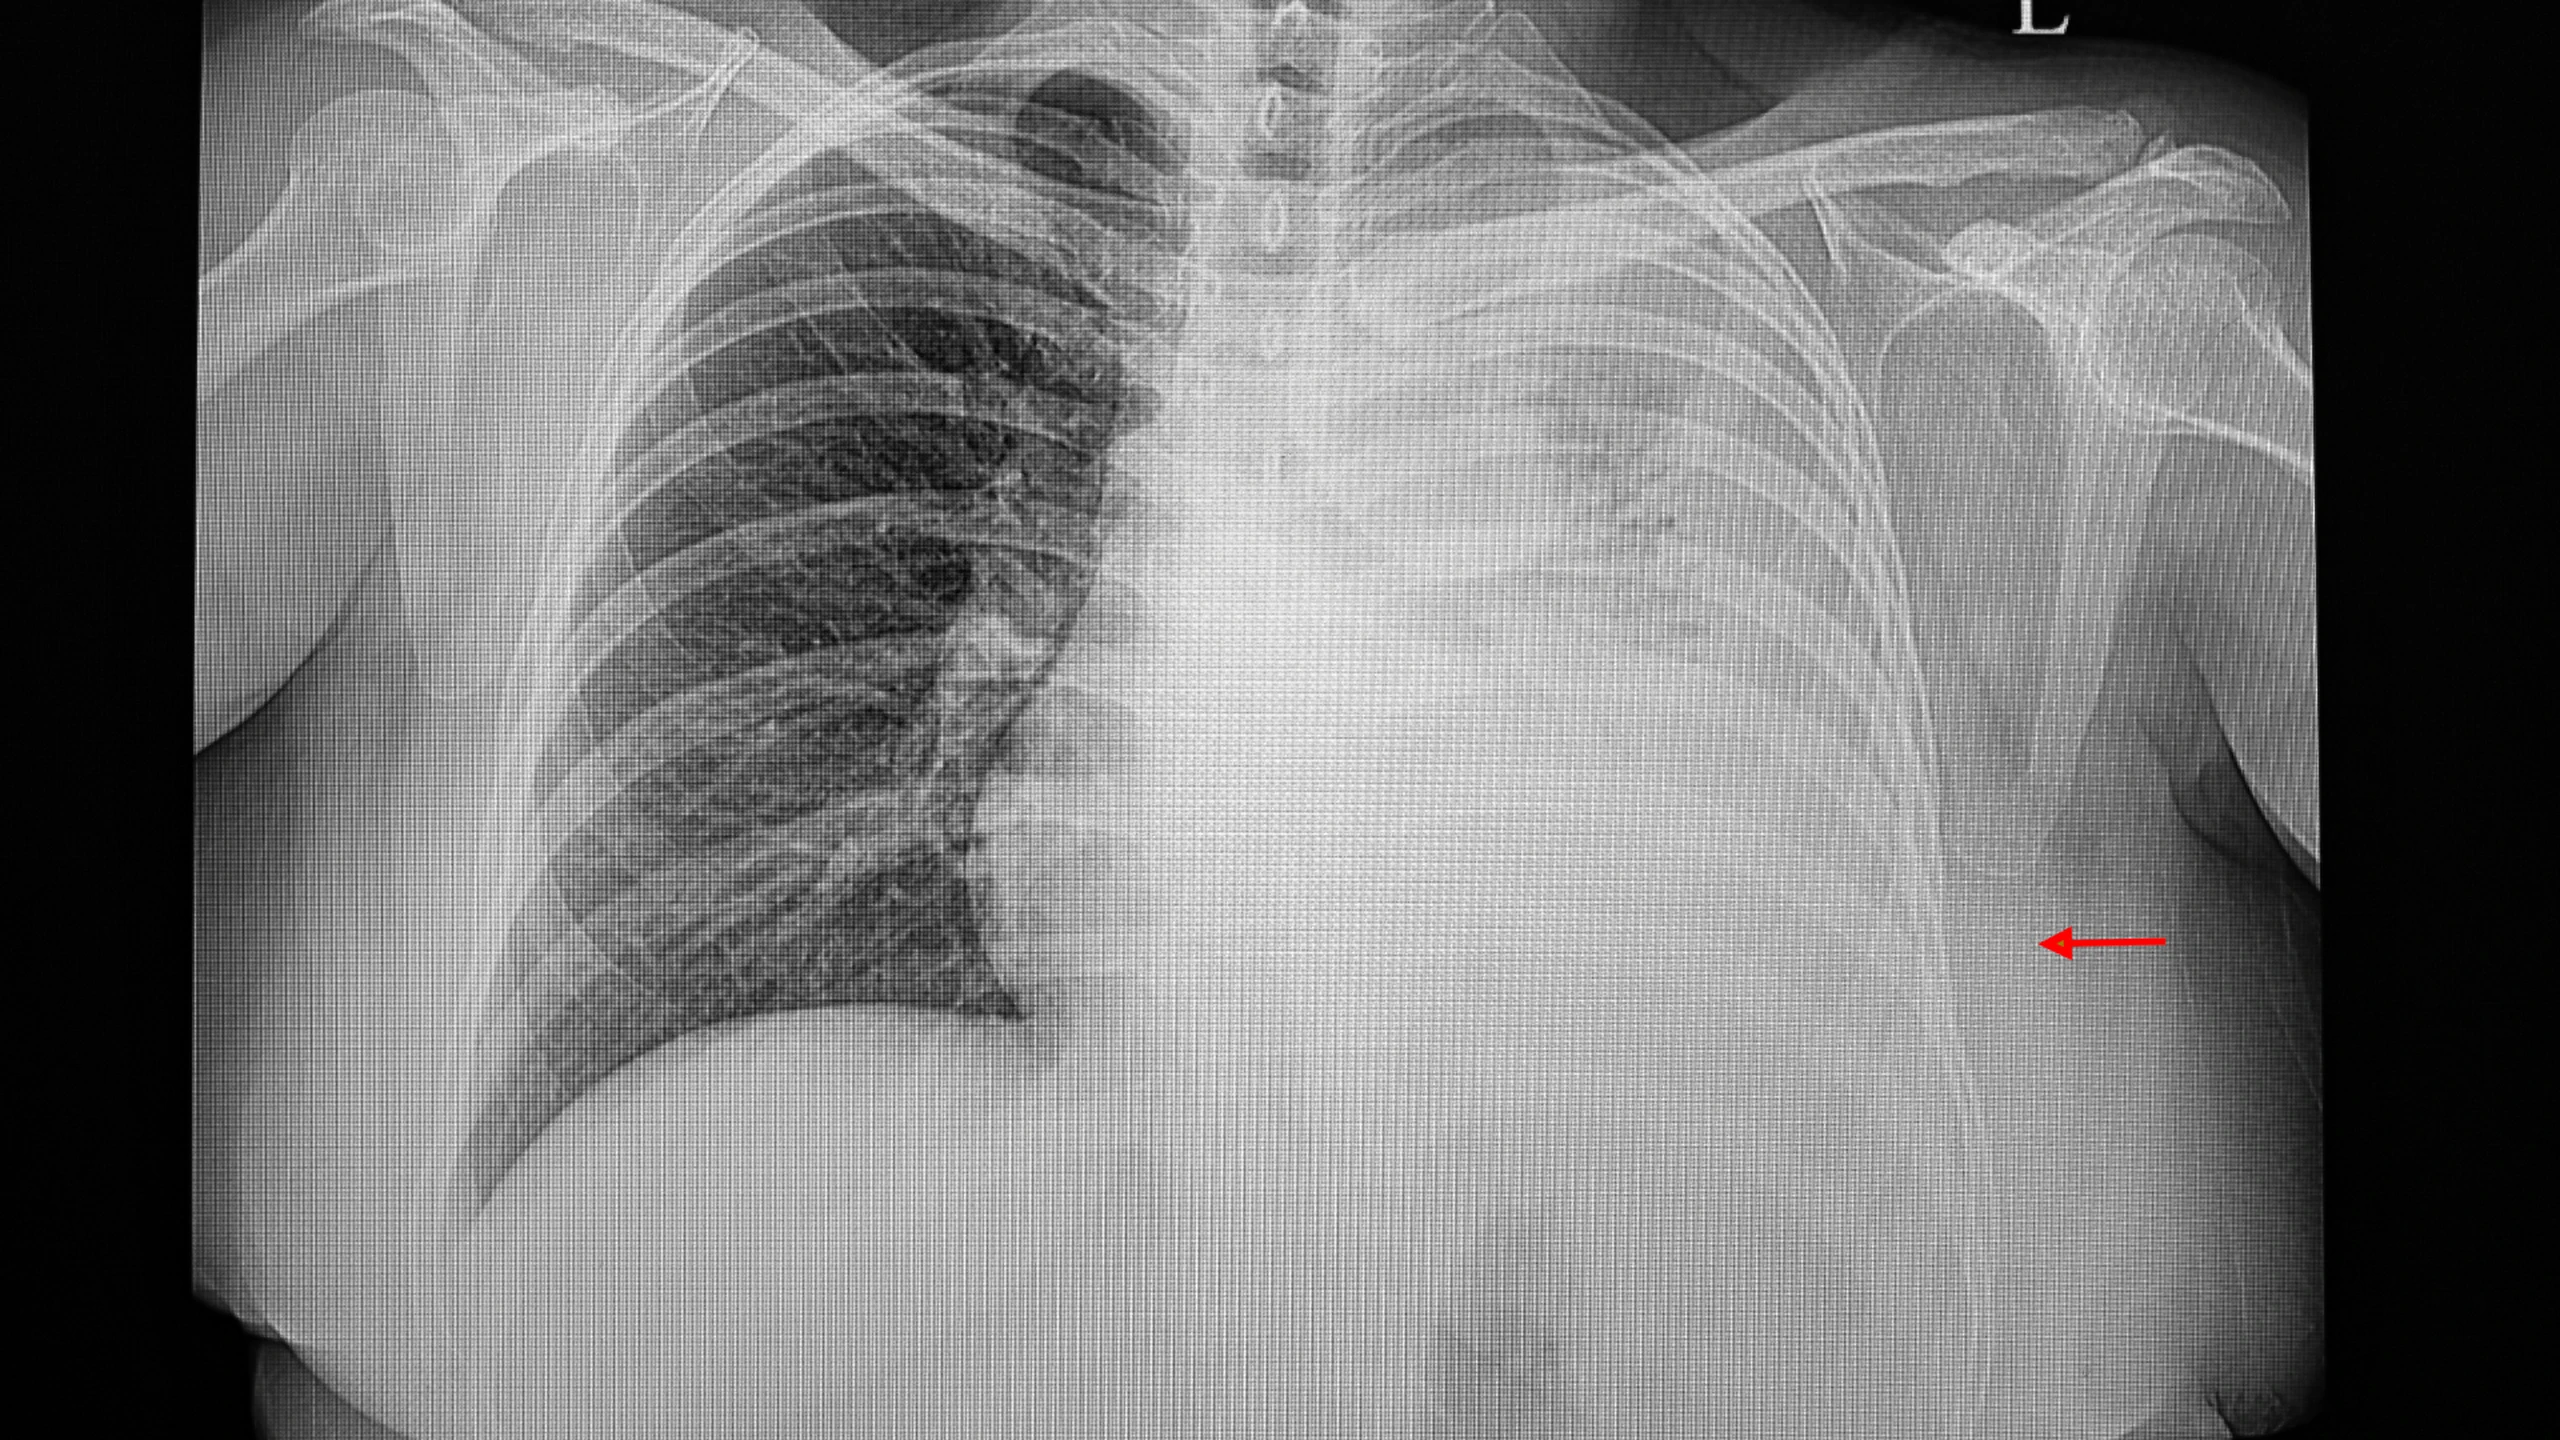

Tràn dịch màng phổi là tình trạng lượng dịch trong khoang màng phổi vượt quá mức bình thường, gây khó thở hoặc đau ngực. Mặc dù có thể không gây triệu chứng khi lượng dịch ít, nhưng khi dịch nhiều, nó có thể đe dọa tính mạng. Tràn dịch màng phổi có thể do nhiều nguyên nhân, cả lành tính và ác tính.

Tuy nhiên, cũng có nhiều bệnh nhân bị tràn dịch không có triệu chứng, chỉ phát hiện được qua phim chụp X quang khi kiểm tra một bệnh khác.

Chẩn đoán có thể được thực hiện dựa trên các biểu hiện lâm sàng của bệnh nhân, kiểm tra hình ảnh ngực (bao gồm chụp X-quang ngực, CT) và kiểm tra siêu âm. Tuy nhiên, việc chẩn đoán nguyên nhân tràn dịch màng phổi, đặc biệt là xác định tràn dịch màng phổi lành tính và ác tính đòi hỏi phải kết hợp các xét nghiệm sinh hóa, enzyme, miễn dịch và bệnh lý tràn dịch màng phổi để chẩn đoán rõ ràng.